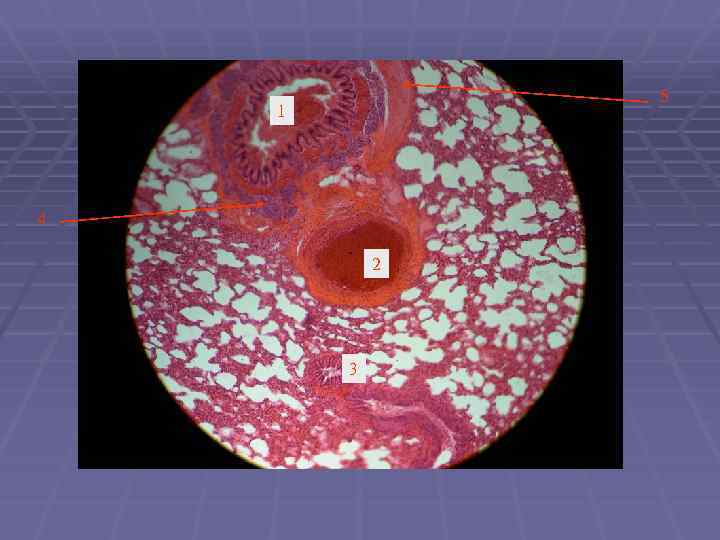

5 1 4 2 3